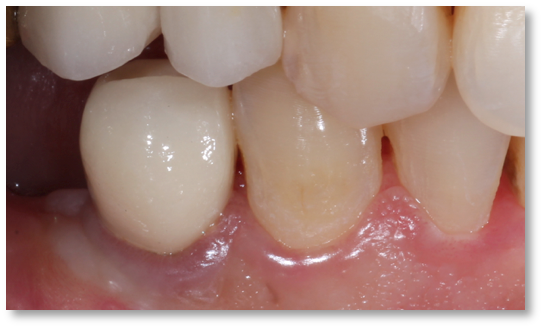

Before and after Periodontal Therapy

| Untreated severe gum disease | Gum disease treated and stabilised by Dr Halai |